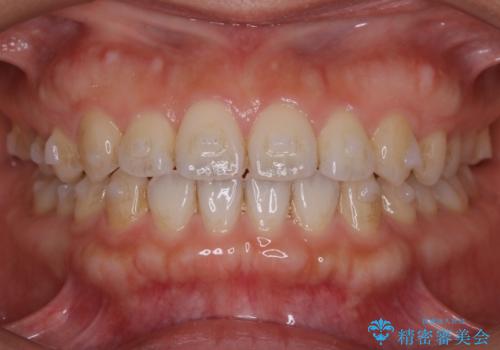

- マウスピース(インビザライン)

- 1年6ヶ月

- 10-30回

初診時の写真では一見噛み合わせには問題がないように見えても、実際に精密な検査を行うと改善すべき点が見つかる場合も多くあります。

当院では、矯正治療は見た目の改善が主目的ではなく機能面を改善し自然に長持ちする口腔内環境を整えることに重きを置く必要があると考えます。